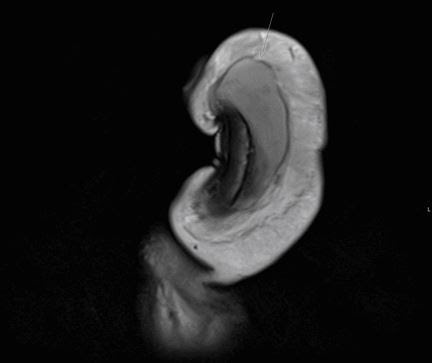

Ao analisar os resultados de uma ressonância magnética, os médicos descobriram que o pênis do homem apresentava um rasgo vertical de três centímetros de comprimento no lado direito.

Estava no meio do tronco, e não em um rasgo horizontal.